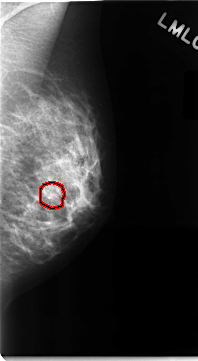

C_0090_1.LEFT_MLO

LEFT_MLO LINES 4688 PIXELS_PER_LINE 2568 BITS_PER_PIXEL 12 RESOLUTION 50 OVERLAY

FILE: C_0090_1.LEFT_MLO.OVERLAY

TOTAL_ABNORMALITIES 1

ABNORMALITY 1

LESION_TYPE CALCIFICATION TYPE PLEOMORPHIC DISTRIBUTION CLUSTERED

ASSESSMENT 4

SUBTLETY 4

PATHOLOGY MALIGNANT

TOTAL_OUTLINES 1

BOUNDARY